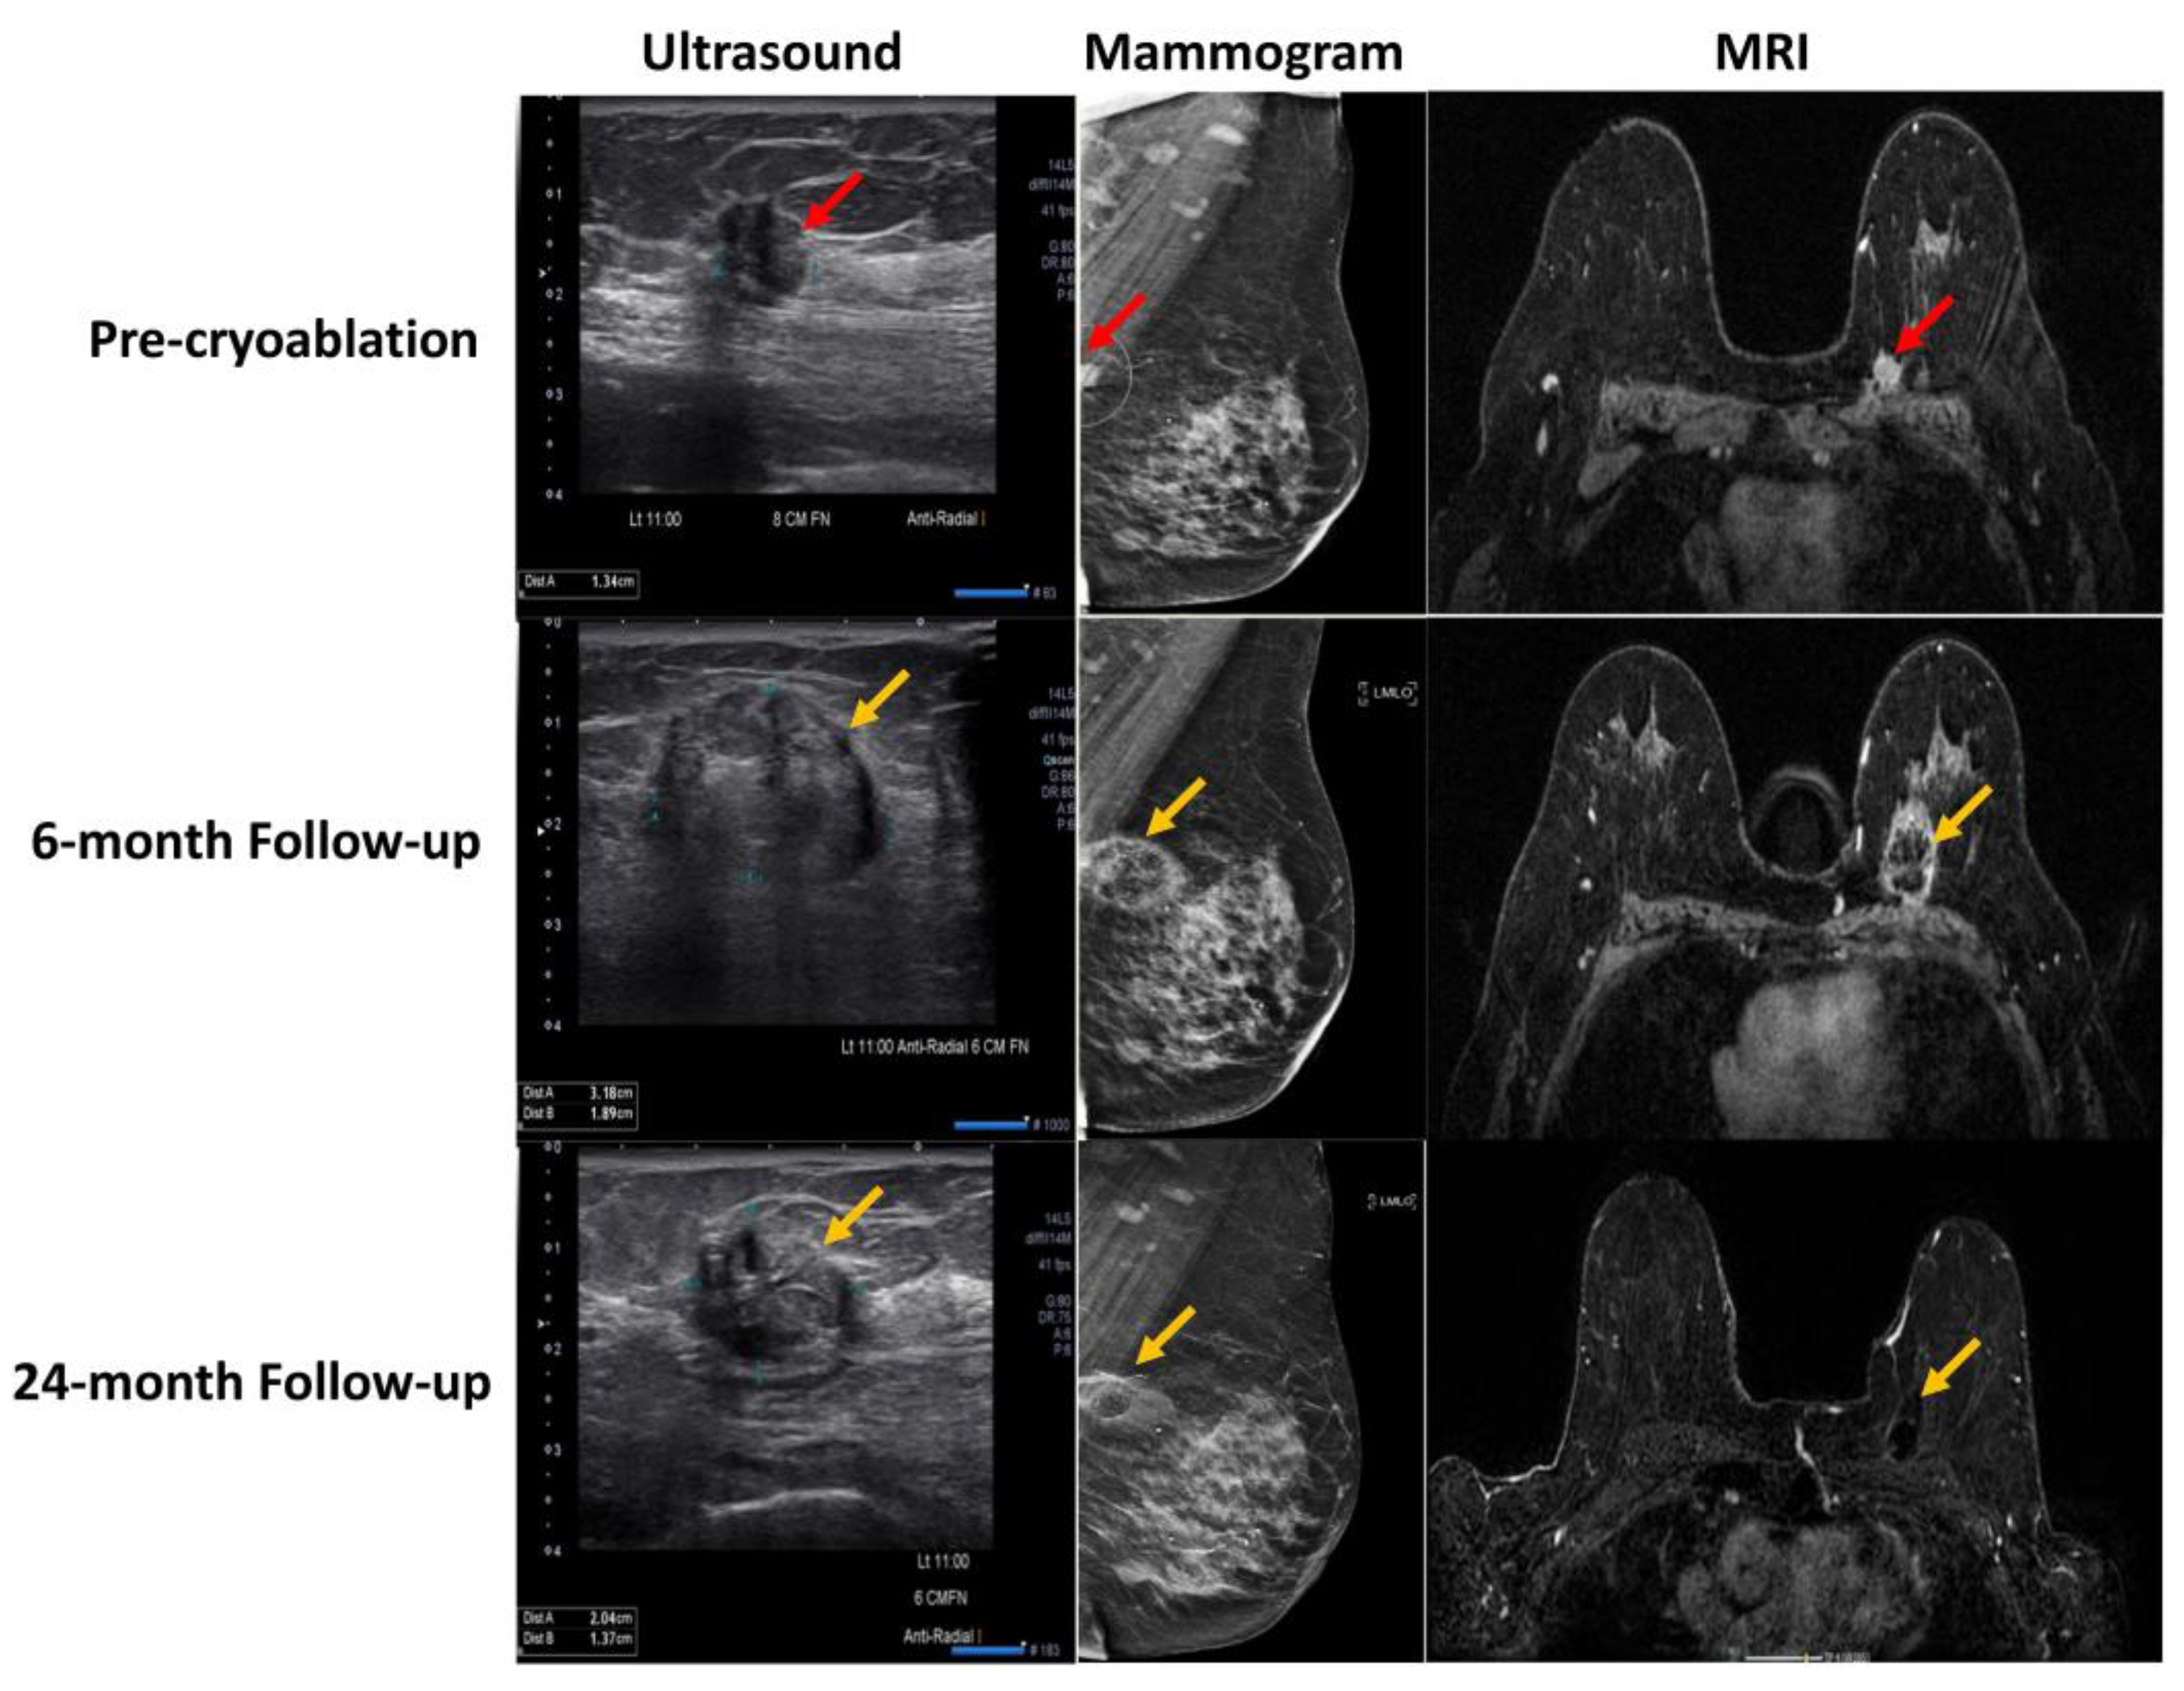

- Ward, R.C.; Lourenco, A.P.; Mainiero, M.B. Ultrasound-Guided Breast Cancer Cryoablation. Am. J. Roentgenol. 2019, 213, 716–722. [Google Scholar] [CrossRef]

- Habrawi, Z.; Melkus, M.W.; Khan, S.; Henderson, J.; Brandi, L.; Chu, V.; Layeequr Rahman, R. Cryoablation: A Promising Non-Operative Therapy for Low-Risk Breast Cancer. Am. J. Surg. 2021, 221, 127–133. [Google Scholar] [CrossRef] [PubMed]

- Machida, Y.; Shimauchi, A.; Igarashi, T.; Fukuma, E. MRI Findings After Cryoablation of Primary Breast Cancer Without Surgical Resection. Acad. Radiol. 2019, 26, 744–751. [Google Scholar] [CrossRef]